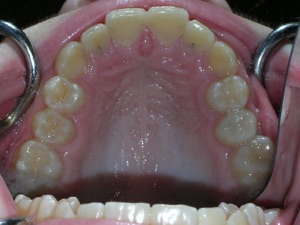

Here’s a fascinating case of a young lady who had a completely blocked out premolar.

With a combination of braces, expansion and trimming we were able to bring it in. Watch!

Here are the results.